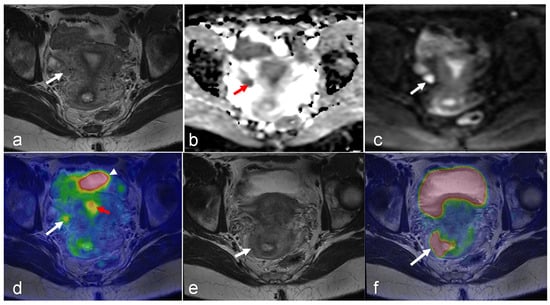

3.3. Ovarian Cancer